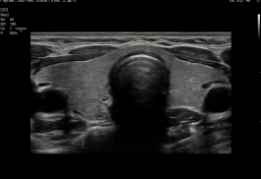

Redefiniendo la imagen con Crystal Architecture™

El Samsung V7 incorpora Crystal Architecture™, una plataforma de imagen avanzada que integra CrystalBeam™ y CrystalLive™, optimizada por sondas S-Vue™. Esta arquitectura permite imágenes más limpias, nítidas y de alta resolución, mejorando la confianza diagnóstica en obstetricia, ginecología, cardiología y aplicaciones generales.

CrystalBeam™ mejora la resolución y uniformidad de imagen mediante formación avanzada de haces, incluso en estructuras profundas o difíciles de visualizar.

CrystalLive™ ofrece renderizado 3D y procesamiento de señal de color mejorados, facilitando diagnósticos complejos y optimizando el flujo de trabajo.

Exquisita calidad de imagen para una mayor fiabilidad y confianza

Mejore su apreciación sobre la evaluación del problema basado en un rendimiento de imagen excepcional impulsado por el motor de imagen principal de Samsung, Crystal Architecture™. El motor de imagen premium combina las ventajas del procesamiento de imágenes 2D mejorado y la expresión detallada del procesamiento de la señal de color. El V7 proporcionará una calidad de imagen sobresaliente para un diagnóstico de confianza.